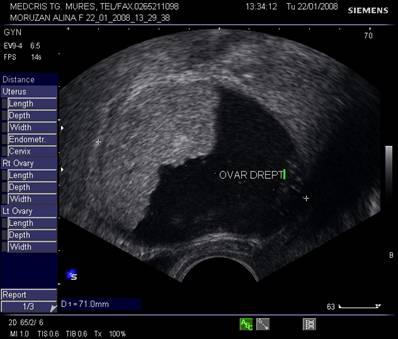

Ovarele. Sectiunea longitudinala directa, spre peretele lateral pelvin, la ecografia transvaginala, pune in evidenta ovarele cu forma elipsoidala. Acestea au structura ecografica relativ slab ecogena, in apropierea si sub vasele iliace.[5]

Marimea ovarelor: inainte de menopauza aproximativ 3,5 x 2,5 x 1,5 cm si aproximativ 2,0 x 1,5 x 1 cm dupa menopauza. Nu se poate aprecia volumul ovarian decat masurand cele trei diametre in planuri sagitale, oblice si coronale ale pelvisului.[1,2,9]

Fig. nr.395.Plex venos dilatat , parametral ( diagnostic diferential cu un chist ovarian, dificil uneori , la ecografia transvaginala )